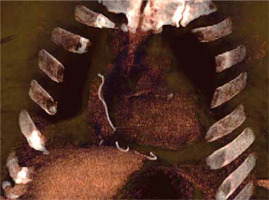

The patient did not develop fever but her blood count showed the normal range of hemoglobin, 11 g/dl, increase of white blood cell count, 12,500 per µl, and C-reactive protein level of 70 g/l. As the swelling kept draining and growing despite antibiotic therapy and serial medication, the patient was hospitalized once again in January 2019 to remove the granuloma surgically. During the post-operative follow-up the wound initially presented with a superficial dehiscence that eventually reached the deep edges of the wound; therefore a computed tomography (CT) scan was performed and it revealed the presence of a foreign body in the patient’s mediastinum which appeared to be the retained TEPWs (Figures 2–4).

Figure 2

Computed tomography (CT) scan images of the retained wires in the subcutaneous tissues of the patient (axial plane)